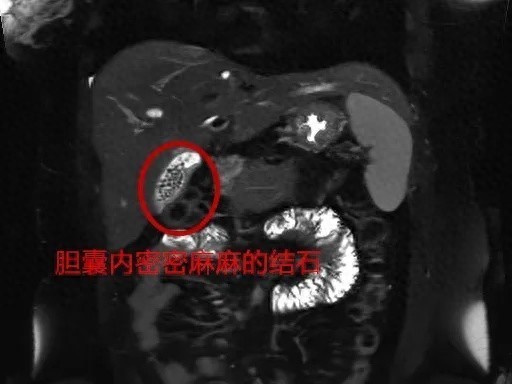

1月20日,宁波31岁的刘女士(化名)在宁波市医疗中心李惠利医院肝胆胰外科完成了胆囊结石的微创手术。3天前,刘女士因腹痛、恶心、呕吐等症状,来到李惠利医院急诊科就诊。经过初步检查,她被诊断为胆囊结石伴急性胆囊炎。医生了解到,刘女士已婚已育,体型偏胖,平时喜欢喝奶茶、吃油腻的食物,检查发现刘女士的胆囊内竟然有充满着大量结石。考虑到患者已有明显腹痛症状,前来会诊的肝胆胰外科王珂副主任医师团队当机立断对刘女士收住入院,需要经过消炎、止痛等治疗后进行腹腔镜下胆囊切除术治疗。手术过程中,外科团队将切除的胆囊打开一看,只见里面密密麻麻,满是形状不一、大小不规则的结石,足足有近百颗。